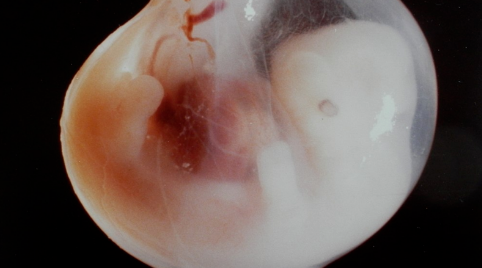

They say that they transformed the genes of the monkey embryo by implanting the genes of a human in order to be able to develop organs in the embryo. They deactivated the genes of the monkey embryo in the procedure.

After that, they implanted human stem cells in the embryo. Human stem cells are responsible for the building of the tissues and they can create any kind of tissues in a body.